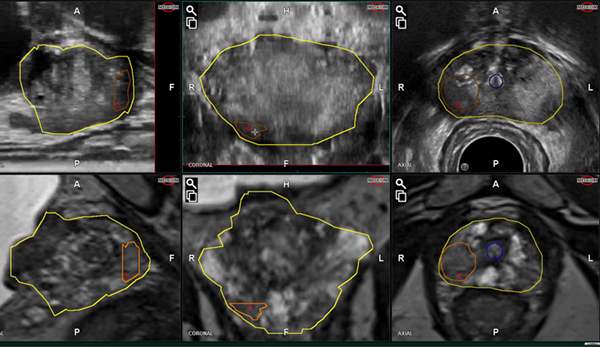

また、前立腺超音波を使用して前立腺の位置を特定し、周囲の組織を損傷することなく前立腺に針を挿入することに成功する場合もあります。

- 泌尿器科医は、潤滑油を塗った小型の超音波装置を直腸に挿入し、前立腺とその周囲の組織を観察します。

- 会陰が麻痺したら、泌尿器科医は陰嚢を持ち上げ、超音波ライブ画像で前立腺に到達していることが確認できるまで会陰に小さな針を挿入します。

泌尿器科医は、経会陰的前立腺生検の前に前立腺の MRI 画像検査を受けるように依頼する場合もあります。この画像検査により、前立腺にがんの兆候がないか検査することで手術の準備に役立つ詳細な多次元画像が得られます。